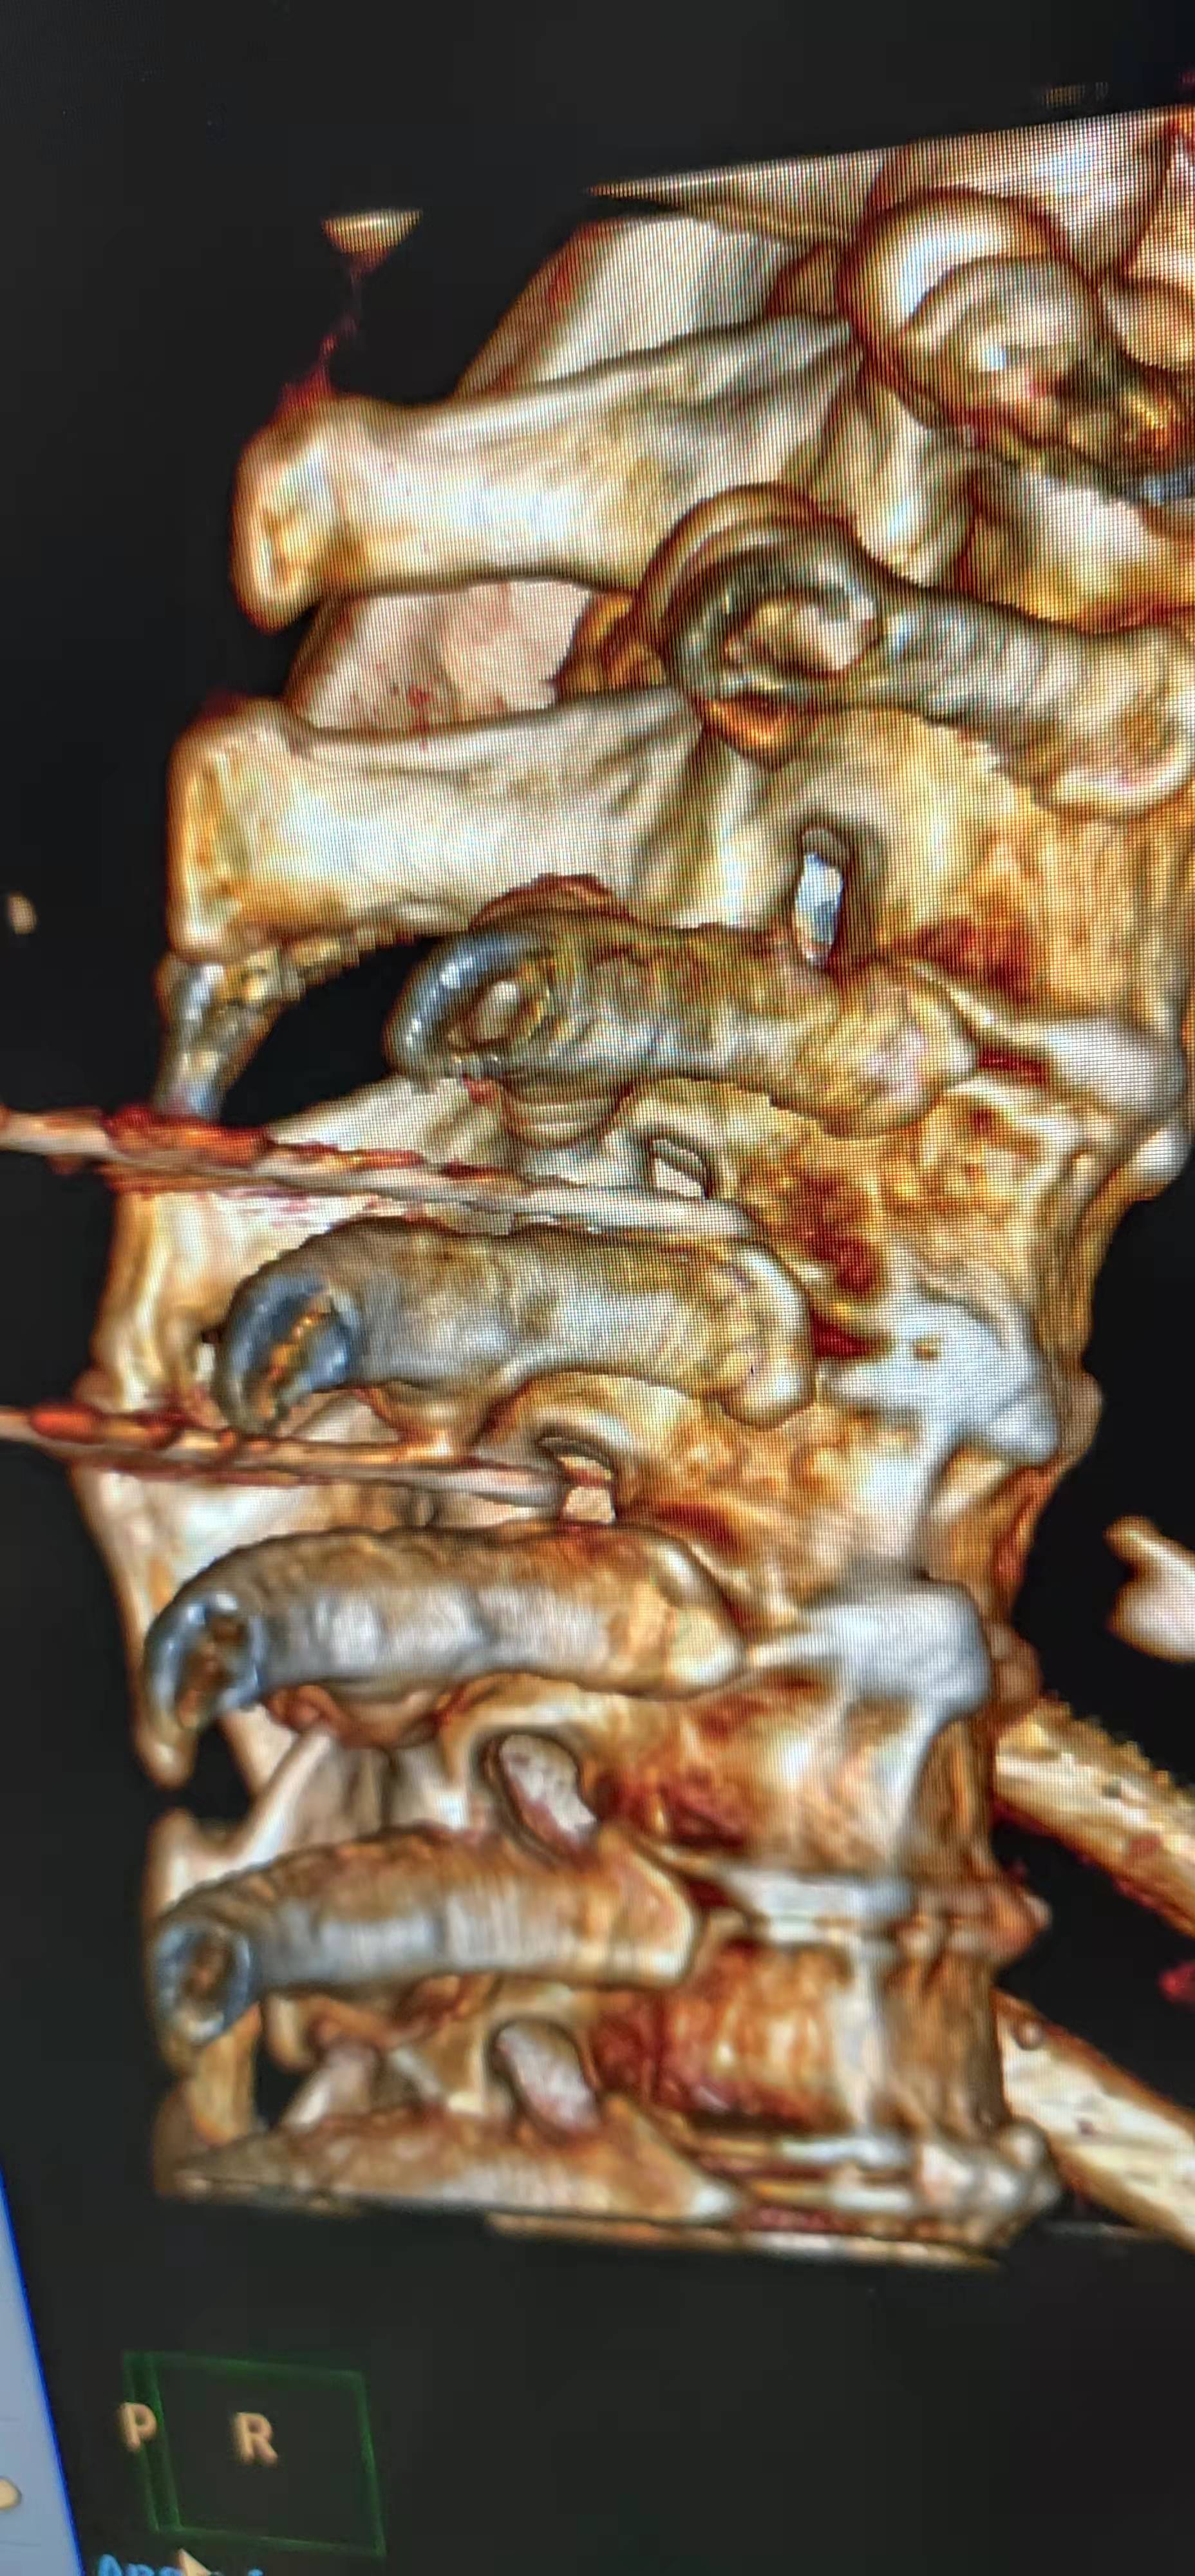

为达成这一目标,田文海主任团队依托该院 3D 打印中心,结合医院先进的大孔径 CT,利用 3D 打印技术可以个体化三维定位引导的优势,为该类患者研制了个体化导板(背根神经节定位穿刺导板),经过多次试验并改进,终于达到了极高的术中定位精准,术中 CT 的引导次数又原来的 5—7 次缩减到 2-3 次。手术时间也缩短到原来的 1/3。

尤其是多节段治疗的患者,更为明显。此外,因为 3D 导板技术使个性化精准穿刺,操作更为简单,学习曲线降低,降低了医生的学习难度,避免了因为远离背根神经节导致疗效不佳,让更多的患者达到最佳的疗效成为可能。